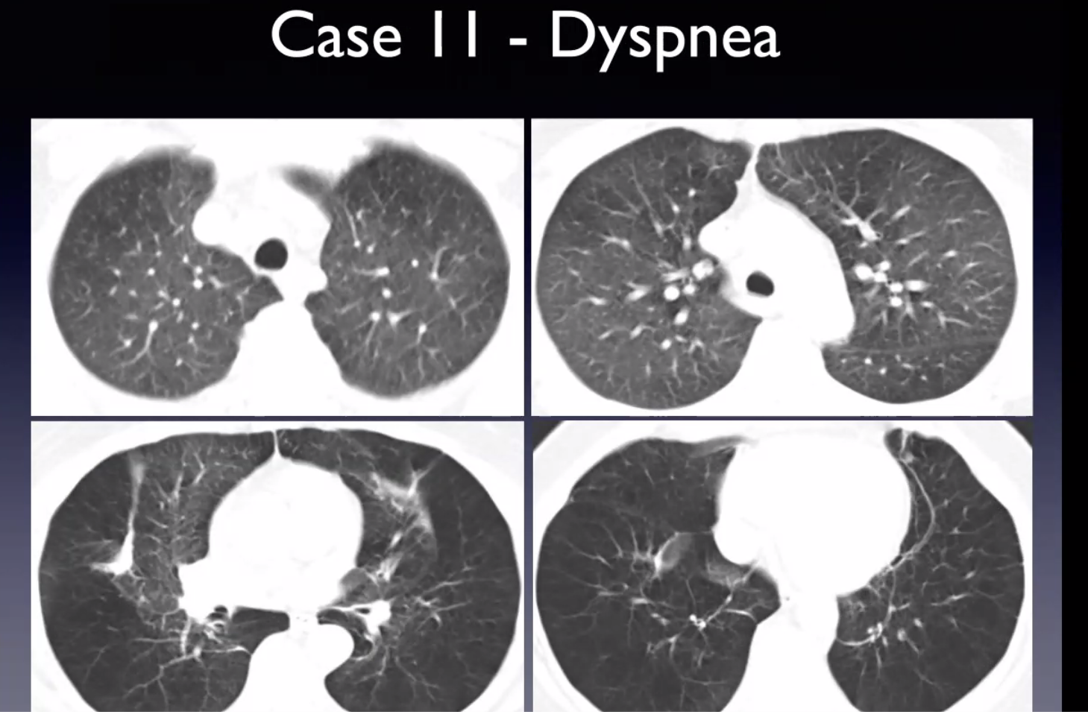

middle aged woman with chronic mild SOB. No smoking history

expiratory HRCT images

Diffuse idiopathic neuroendocrine cell hyperplasia (DIPNECH)

multiple small pulmonary nodules and mosaic attenuating from air trapping due to constrictive bronchiolitis

bronchiolar inflammation